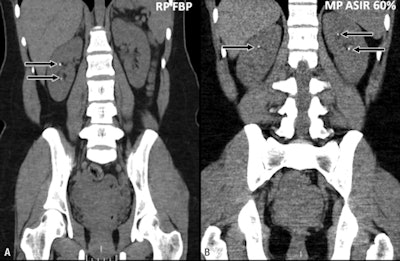

| Coronal CT images acquired in a 28-year-old man (body weight, 73 kg) with renal stone disease. Left (A) baseline reference-protocol (RP) CT image shows two 2- to 3-mm calculi in the right kidney. Right (B) follow-up modified-protocol (MP) CT image obtained six months later and reconstructed with 60% ASIR demonstrated two new tiny stones in the left kidney and a single calculus in the right kidney. The patient probably passed the inferiorly located calculus, which was not visualized at follow-up CT. The tiny renal calculi are depicted equally well on ASIR-reconstructed images and baseline CT images. Images republished with permission of RNSA from Radiology. |

In 13 of the 25 patients, prior standard-dose scans had also been performed with a 16-detector-row CT scanner (LightSpeed 16, GE) and a conventional FBP reconstruction technique. These 13 patients, who served as a reference protocol group for the study, had been scanned with a tube voltage of 120 kV and patient-weight-based tube-current modulation with a tube current range of 75 mA to 250 mA. The noise index was set to 25.

In the modified protocol, the tube voltage was cut from 120 kV to 80 kV for patients weighing less than 200 lb (and to 100 kV for those weighing more). The automated tube-current modulation technique was set to 75 mA to 150 mA with a noise index of 30 for both groups. The researchers created one FBP and two ASIR (60% and 80%) image sets.

The results showed overall low-quality images for the modified protocol at FBP reconstructions (mean image quality, 2.5), but there was significant improvement with ASIR reconstruction (mean image quality, 3.4; p = 0.03).

For detecting stones using the modified protocol, the diagnostic confidence was higher for 60% ASIR images (mean score, 3.0) and 80% ASIR images (mean score, 3.0) than for FBP images (mean score, 1.9; p = 0.03).